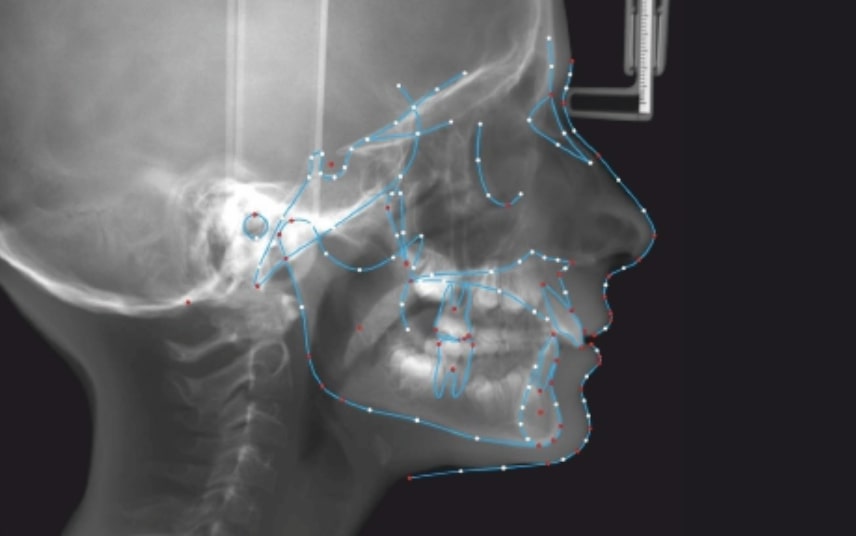

FACIAL: class 2 profile with Lower jaw deficit

SKELETAL PATERN: Class 2

Clinical examination and diagnosis

Malocclusion A6 Correction of Mandibular Retrusion in Growth phase patient | Skeletal Class II | Class II Division 1 malocclusion | Deep bite | Mixed dentition